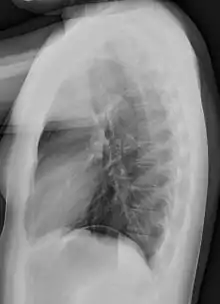

Chest radiograph

A chest radiograph, called a chest X-ray (CXR), or chest film, is a projection radiograph of the chest used to diagnose conditions affecting the chest, its contents, and nearby structures. Chest radiographs are the most common film taken in medicine.